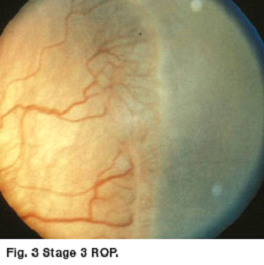

ROP is described by its location in the eye (the zone), by the severity of the disease (the stage) and by the appearance of the retinal vessels (plus disease). The first stage of ROP is a demarcation line that separates normal from premature retina. Stage 2 is a ridge which had height and width. Stage 3 is growth of fragile new abnormal blood vessels. As ROP progresses the blood vessels may engorge and become tortuous (plus disease) [See figures 2 and 3].